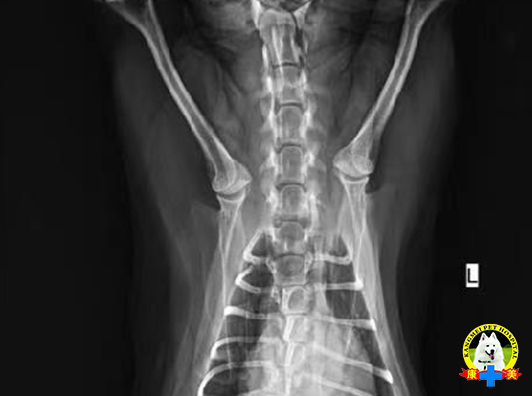

玩具犬 共济失调

1.基础信息 宠物姓名:球球 ,品种:玩具泰迪犬, 体重:2kg, 年龄:2Y ,性别:♀。 之前一切正常,昨天晚上外出遛弯回家后比较兴奋,玩耍时从床上掉下,后来就不太愿意动了,到现在,就一直站不起来了。

2. 临床检查 BCS:4/9,T皮:38.5°,HR:96,RR:24 CRT:<2S,MM:pink 患犬俯卧,精神状态焦虑,头部抬起,意识清醒正常;无法正常站立和行走,四肢神经功能障碍,共济失调,四肢悬空时有不自主划水样动作;瞳孔反射正常未见异常震颤或大小不一,脑神经检查未见异常;本体感受减弱。

3.辅助检查 血检结果:传染病阴性,血检无异常,未见中毒指征。DR未见明显寰枢椎脱位(未镇静,摆位可能存在一定误差)。

4. 初步诊断 基本可以判断为脊髓性共济失调,根据患犬品种、发病前24小时的经历,怀疑外力导致的寰枢椎半脱位或椎间盘突出压迫脊髓。

5. 治疗 1、静养,由于动物不愿进食,主人无法喂食,需要住院输液,强饲,保证基本营养摄入; 2、每天90min高压氧理疗; 3、泼尼松龙2mg/kg*day,奥美拉唑1mg/kg*day; 4、四肢肌肉按摩拉伸,每天两次,每次5min;